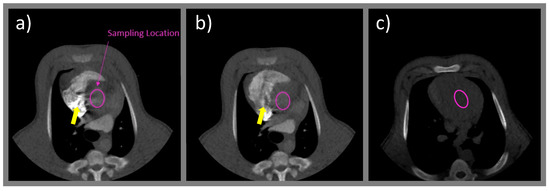

2.3.2. Sampling Location and Unit Conversion